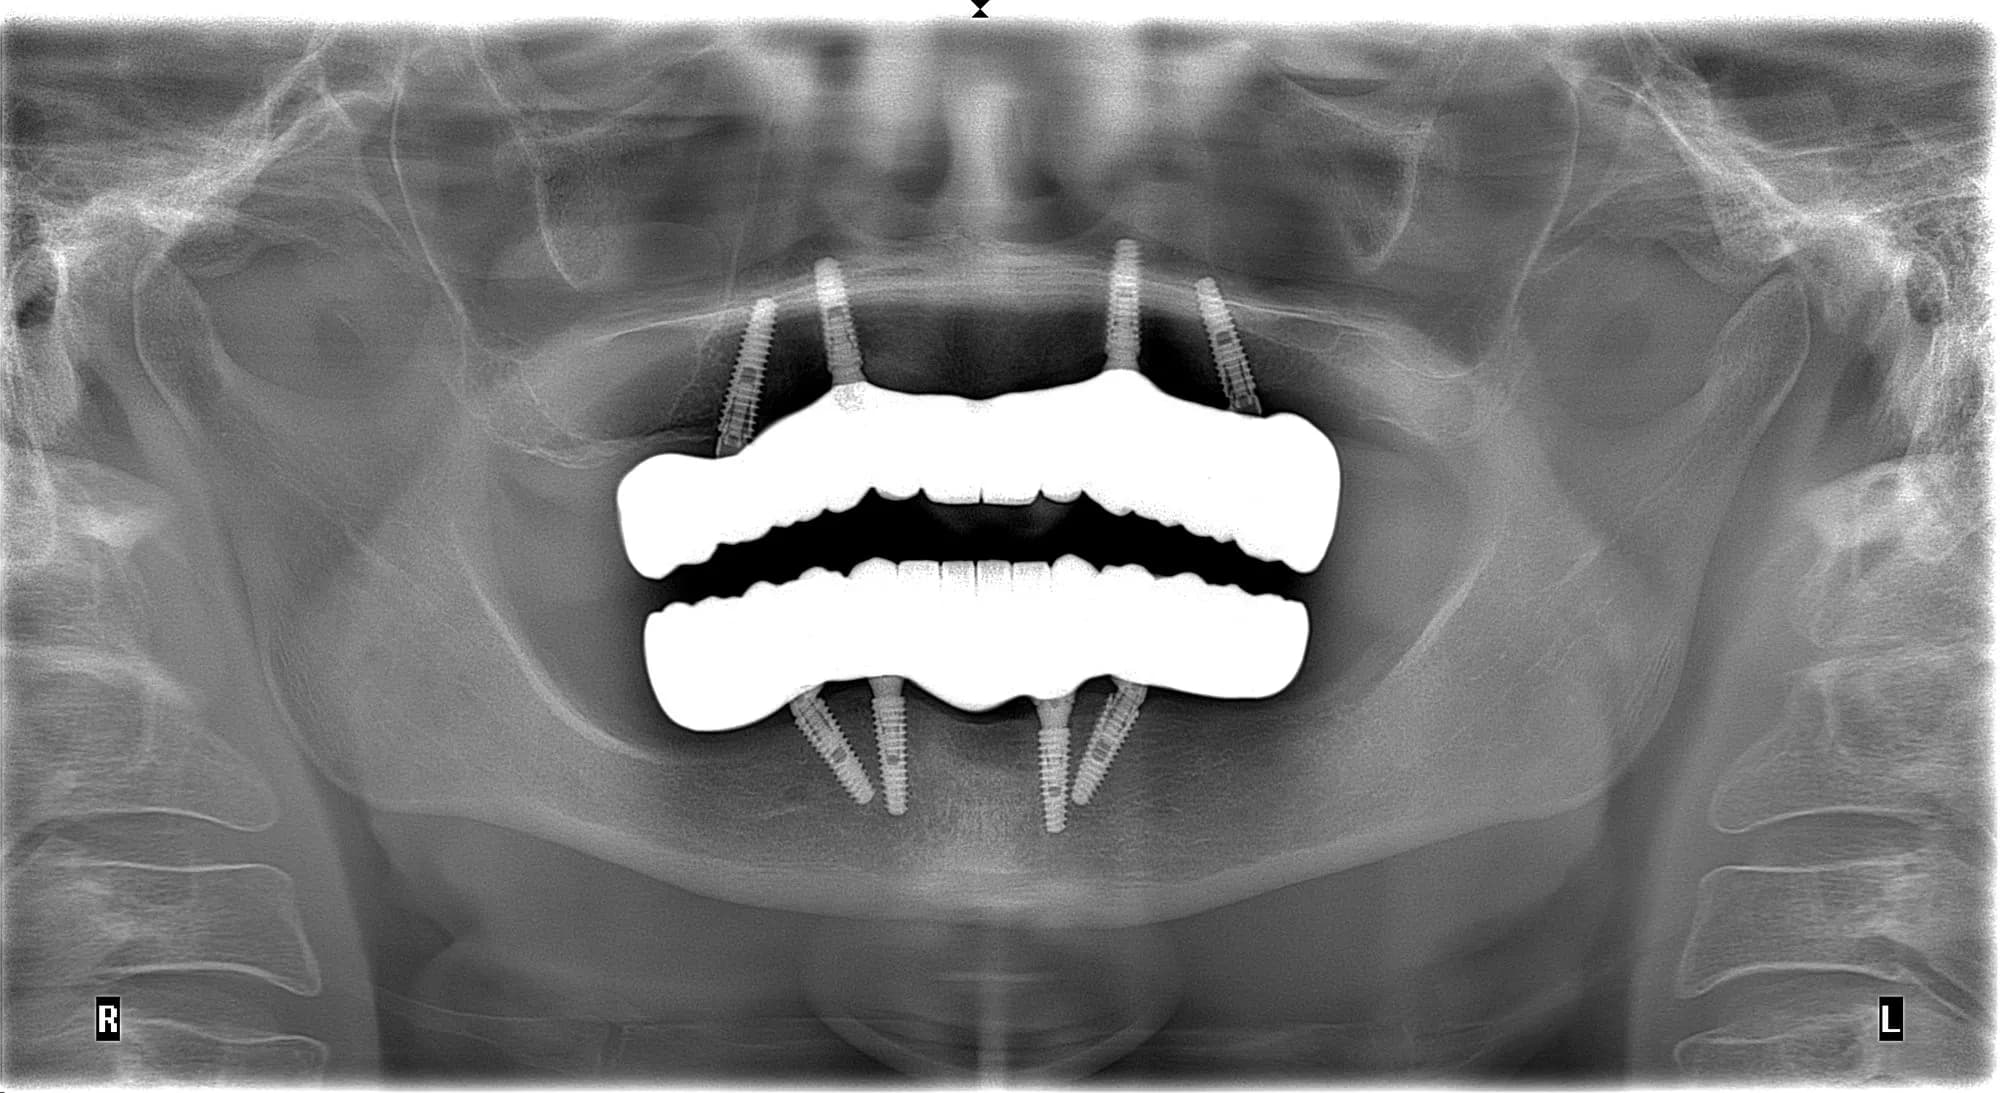

Неякісно проведене протезування на імплантах після тотальної імплантації в іншій клініці. Злам протезів.

Решение

Виготовлення постійної конструкції з цирконію на титанових балках.

Сроки лечения

2 тижні